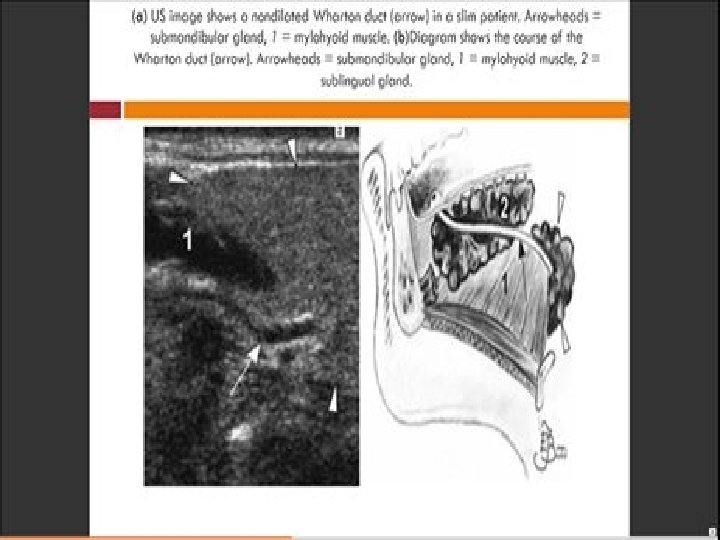

• Ultrasound is also an accurate Modality for measuring the thickness of Muscles, data regarding thickness may provide information useful in diagnosis and treatment especially in. follow up examination. • Ultrasound can also be used for detecting Sialoliths in Parotid, submandibular and sublingual salivary glands, which appear as echodense spots with a. characteristic acoustic shadow • In Ultrasound, color Doppler sonography has been developed to identify vasculatures and to enable evaluation of the blood flow, velocity and vessel resistance together with surrounding Morphology. It can be used for detecting the coarse of the facial artery and for detecting hemangioma.